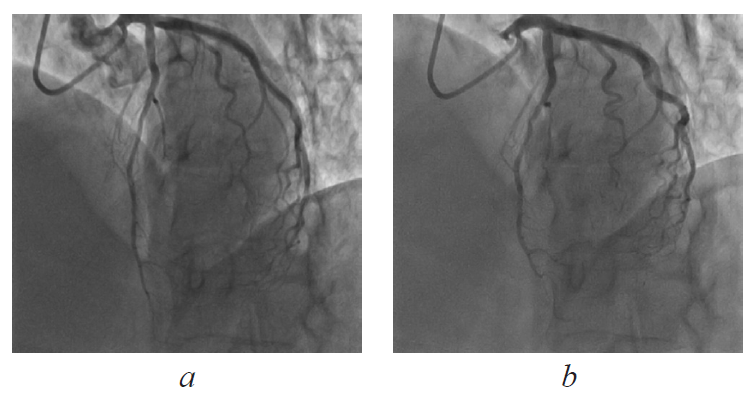

From March 18, 2014 to April 1, 2014, she was treated at a hospital in an emergency for suspected unstable angina. The patient underwent coronary angiography, which revealed a myocardial bridge of the left anterior descending artery with dynamic stenosis of up to 70%, and a small shunt from the pool of the left coronary artery into the left ventricle was revealed using contrast medium (Fig. 1 a, b). Coronary artery stenosis was not detected. On discharge, additional examinations, including Holter ECG monitoring and stress echocardiography, were recommended to the patient. Disaggregants (acetylsalicylic acid), calcium antagonists (amlodipine), diuretics (torasemide), ACE inhibitors, and beta-blockers were prescribed as components of a permanent medical treatment.

Fig. 1. Myocardial bridge of the left anterior descending artery (coronary angiography) diastole (a), systole (b)

Рис. 1. Мышечный мостик передней нисходящей артерии (коронарная ангиография) в диастолу (a) и в систолу (b)